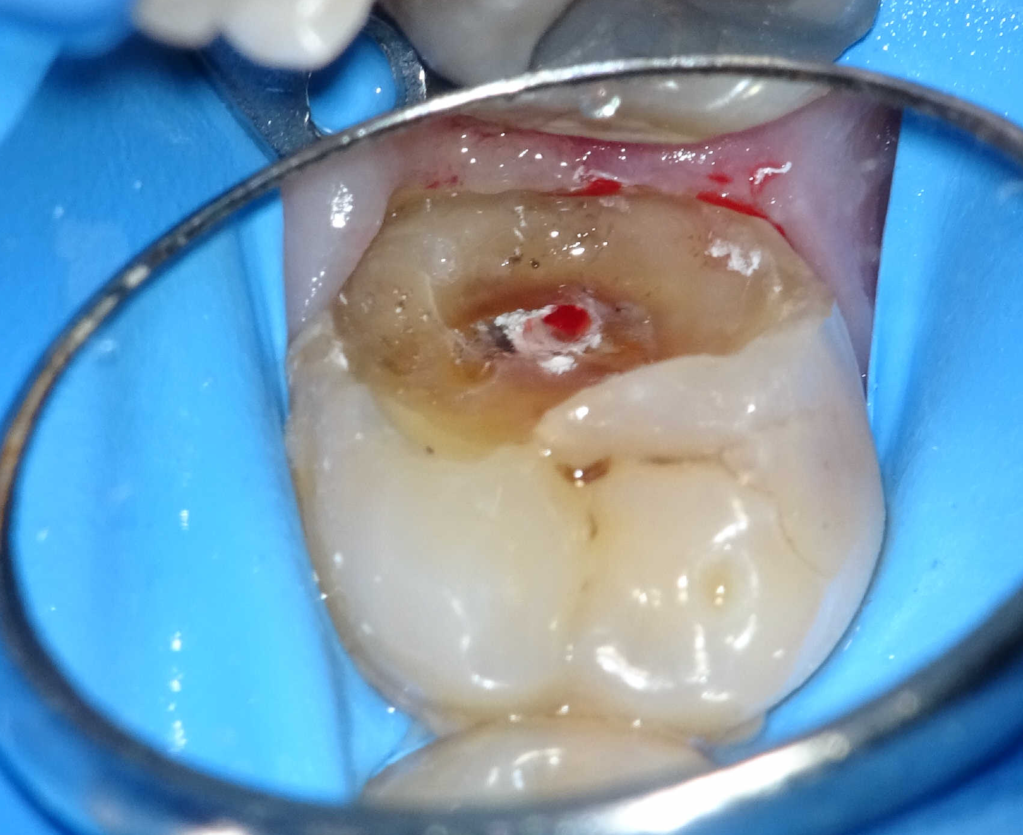

Pulpotomía biodentine + reco preendio